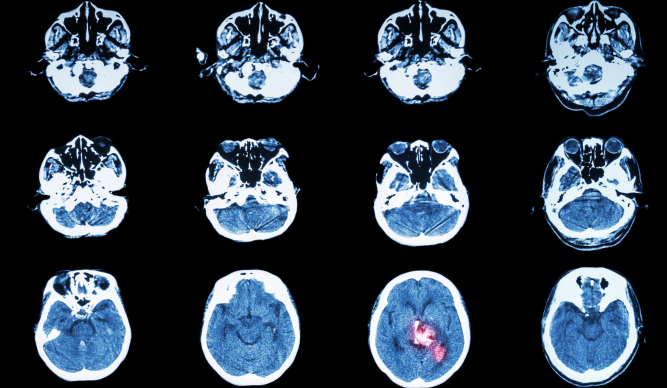

Le centre NEURI est une plateforme lourde de neuroradiologie offrant des consultations, des hospitalisations et la réalisation d’interventions non invasives, sous contrôle radiologique. Il permet  le diagnostic et la prise en charge, notamment en urgence, de patients atteints de maladies vasculaires du cerveau et de la moelle épinière (dont les ischémies cérébrales). La thrombectomie, correspondant à une extraction de caillots des artères intracrâniennes, est par exemple l’une des techniques utilisées par des équipes de NRI pour soigner certains accidents vasculaires cérébraux.